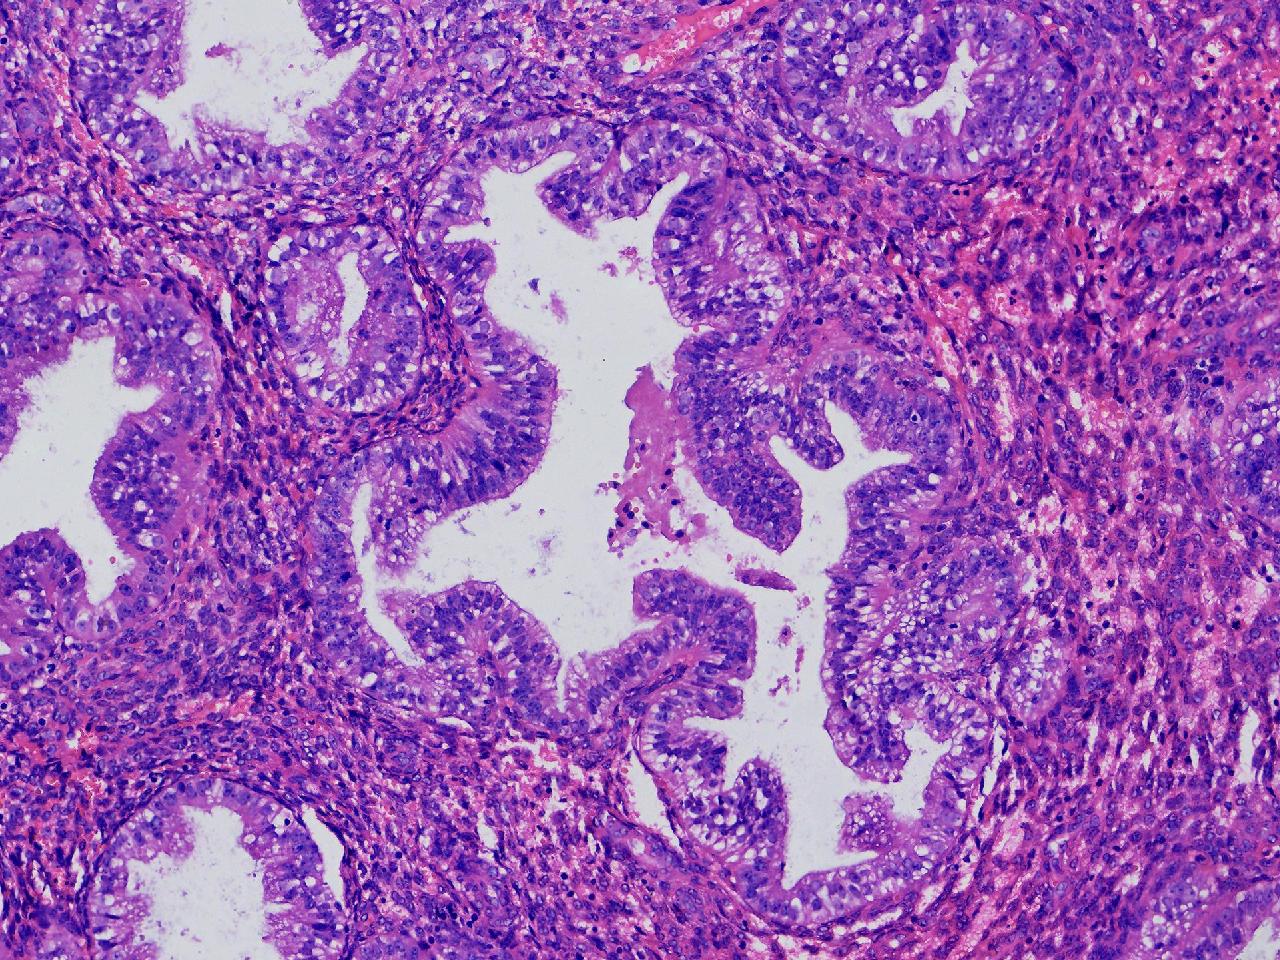

请教诊断.有没有非典?

性别

女

年龄

50岁

女,50岁,彩超示:内膜厚1.3cm。

子宫内膜

灰粉色不整形软组织多块,2X2X1厘米。

无非典型性子宫内膜增生

无非典。